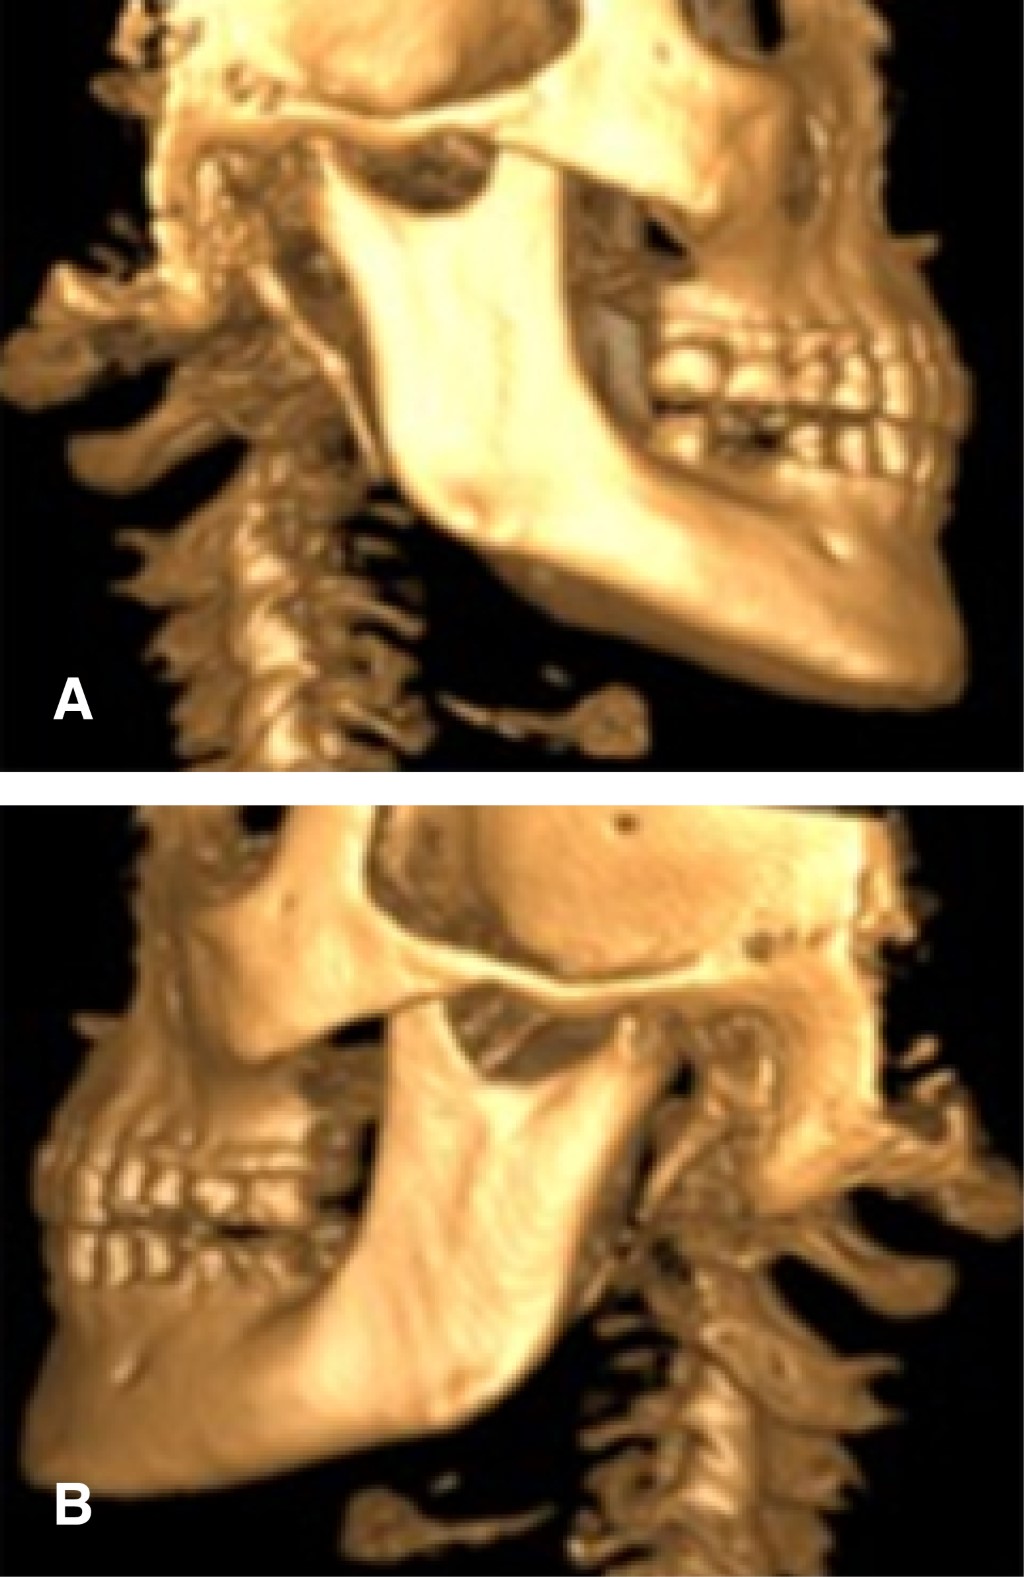

The majority of the affected patients show no symptomatology, although the pressure exerted by this altered structure against neighboring structures can trigger a wide variety of symptoms3 (Figure 1).

In addition, the relationship between the length of the SP and the characteristic symptoms of Eagle syndrome was assessed (Figure 3).

Figure 1

Figure 3